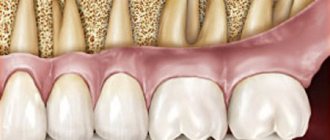

A cyst in the maxillary sinuses appears as a result of complete occlusion or significant problems with the outflow of secretions from the gland (which regularly produces mucus). In the international classification of the disease, a maxillary sinus cyst is classified as a retention disease.

With an intraoral gairotomy, the otolaryngologist makes a horizontal incision in the soft tissues of the upper gum and moves them upward. Then, using special instruments, part of the bone plate on the facial wall of the maxillary sinus is removed. Thanks to the hole made, the sinus cavity becomes accessible for manipulation, and the otolaryngologist removes the pathological contents using a sharp spoon.

After scraping the mucous membrane, an anastomosis is formed with the nasal cavity, smoothing out the bone defect. A flap is made from the remaining free mucosa and placed on the bottom of the maxillary sinus to restore epithelization of its walls.